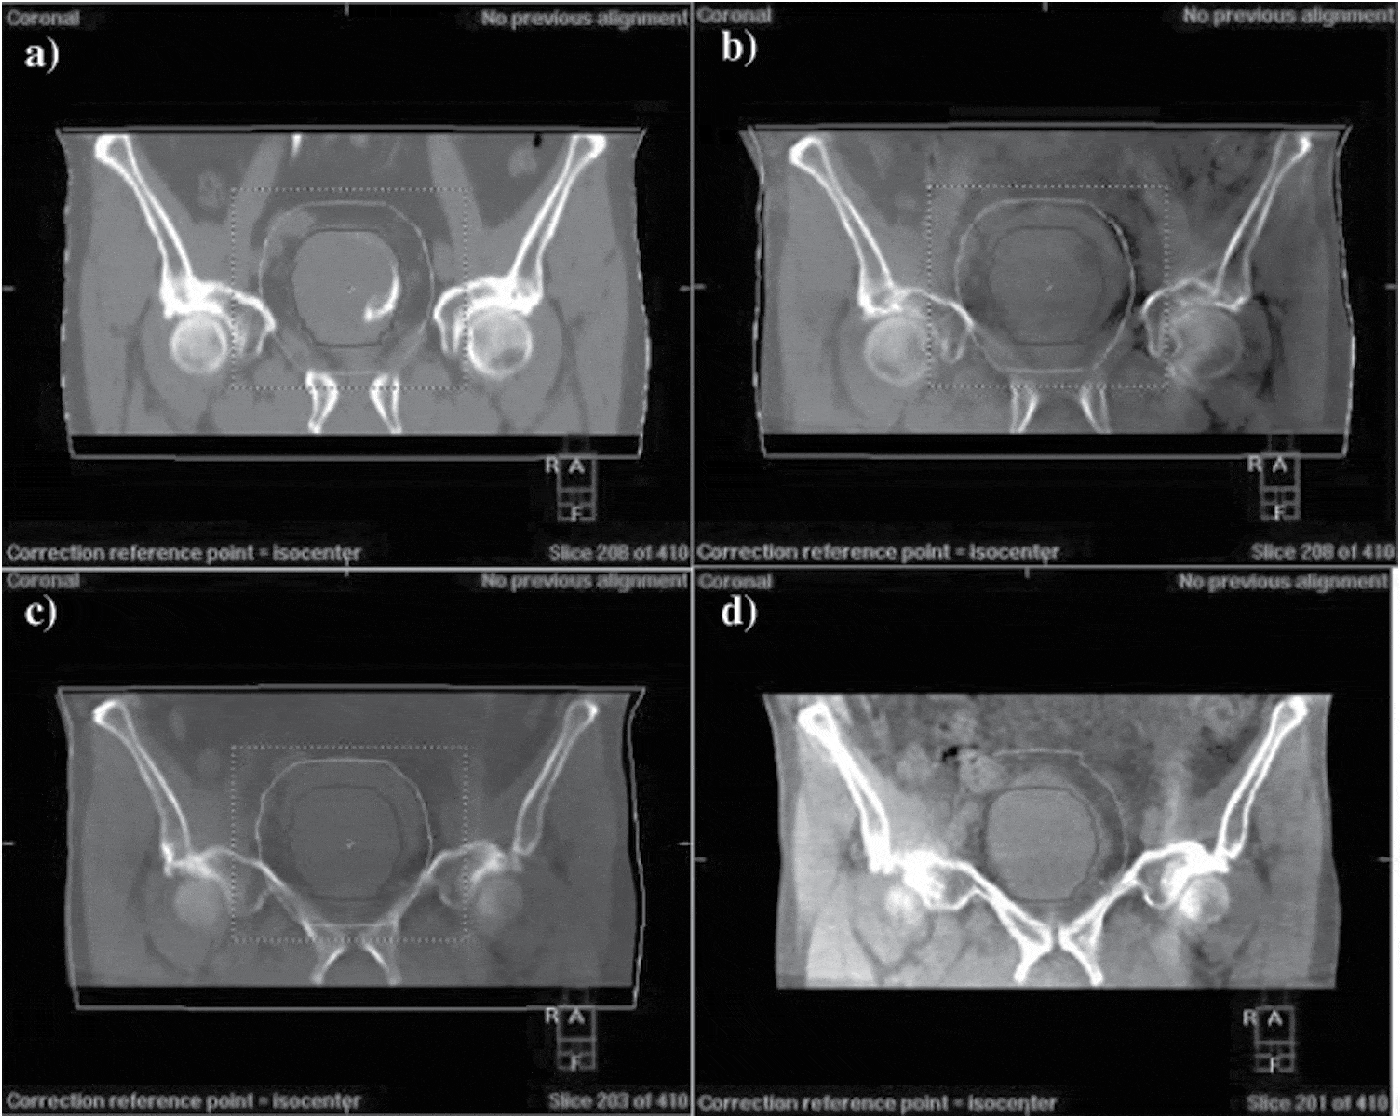

From www.cambridge.org

Delivering adaptive radiotherapy to the bladder during radical treatment Journal of Bladder Stimulator Surgery With the interstim™ system, you can try the therapy for about a week before you decide whether or not to have a device implanted for. It uses a mild electric current to treat your overactive bladder (oab) and ease your strong urge to pee. Overactive bladder (oab) the nuro™ device administers a therapy called percutaneous tibial neurostimulation (ptnm). Offices in. Bladder Stimulator Surgery.